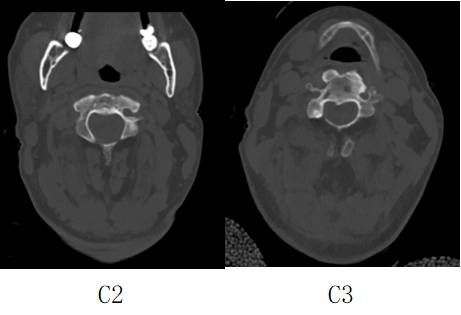

接诊后得知,金先生还患有强直性脊柱炎多年,这种疾病直接的后果是脊柱强直如棍棒,骨质变脆易骨折,被冠名以“不死的癌症”。姜主任详细了解金先生的病史后,认为该患者的治疗关键在于以下三个方面:一是脊柱强直,手术部位的位置深难以显露,解剖复杂。二是C2、C3左侧椎弓根发育异常狭小,置入椎弓根螺钉困难。三是齿状突骨折向后方移位明显,通常向前脱位较为常见复位也较容易,此种脱位的复位具有较大的难度和损伤脊髓的风险,对于术者而言是个巨大考验。

金先生伤后第7天,姜主任医师团队在麻醉手术科的密切配合下成功为他实施手术。姜主任凭借多年徒手置钉的过硬技术经验,2小时不到便完成了手术,术中出血仅100ml。术后CT显示齿状突完美复位,螺钉“不偏不倚”的位置恰到好处。术后,金先生在骨科护士长张霞芬护理团队的精心护理下,15天后伤口拆线康复出院。